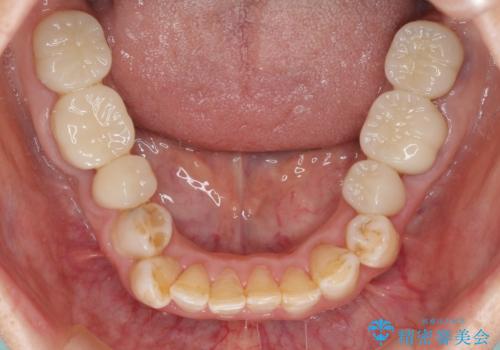

- 全顎的な歯列不正と、銀歯だらけの奥歯を気にして来院された患者様です。

奥歯の銀歯は、セラミッククラウンを装着するには歯の高さが不十分であり、そのままでは矯正治療を行うことが困難であるため、歯冠長延長術を行うこととしました。

また、根管治療の必要な歯がいくつかあるため、歯周外科治療の治癒期間を利用して根管治療を行い、その後インビザラインにて矯正治療を行うこととしました。

矯正治療後にはオールセラミッククラウンにて補綴治療を行うこととしました。

歯冠長延長術を行ったことで、自然な形態かつ清掃性の高いセラミッククラウンを装着することができました。

全顎的に治療を行ったため、治療期間も費用も負担は大きくなりましたが、統一感のある仕上がりとなりました。